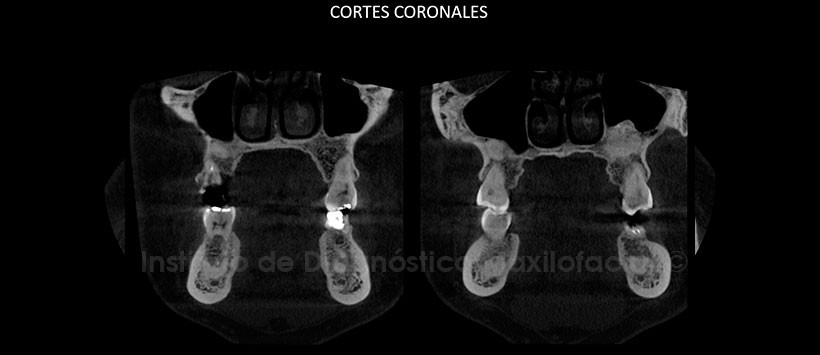

Al estudio mediante tomografía computarizada de haz cónico (CBCT), mediante reformación panorámica (Figura 2), cortes axiales (Figura 3) y coronales (Figura 4) se evidencia alteración del patrón de trabeculado óseo de manera focalizada a nivel apical de las piezas 1.8, 1.7, 2.6, 2.7, 3.5, 3.6, 3.7, 3.8, 4.5, 4.6 y 4.7. Presenta una densidad aumentada compatible con hueso y/o cemento.